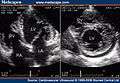

Images

Transthoracic two-dimensional echocardiogram in apical four chamber and parasternal short axis at the level of both ventricles demonstrate dilatation, deep trabeculae and intertrabecular recesses in the inferior, lateral, anterior walls, middle and apical portions of the septum and apex of the left ventricle.